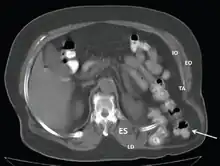

CT scan-Grynfeltt-Lesshaft hernia.